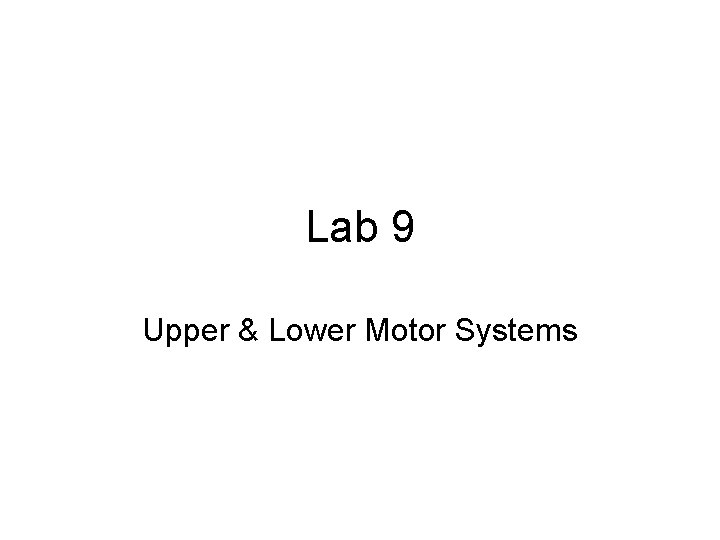

1 SMA Motor planning FEF PMA Motor planning Of voluntary action Prefrontal Cortex • Processing sensory and memory info • Decision making What is the ~location of the: Prefrontal Cortex? PMA (premotor area)? SMA (supplementary motor area) FEF (frontal eye field)

1 2